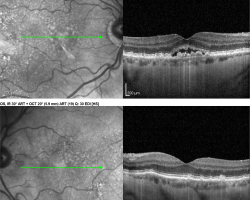

OCT maculaire

- OD : décollement séreux rétinien avec membrane néovasculaire visible (plutôt néovaisseau choroïdien visible). Pas de plage d’atrophie visible sur cette coupe, drusen sereux visibles

- OG : drusen visible, pas de signe exsudatif

- OCT-Angio : modalité d’OCT permettant de ne pas réaliser d’angiographie à la fluorescéine dans certains cas (ici fait le diagnostic de DMLA avec image typique de membrane néovasculaire visible)